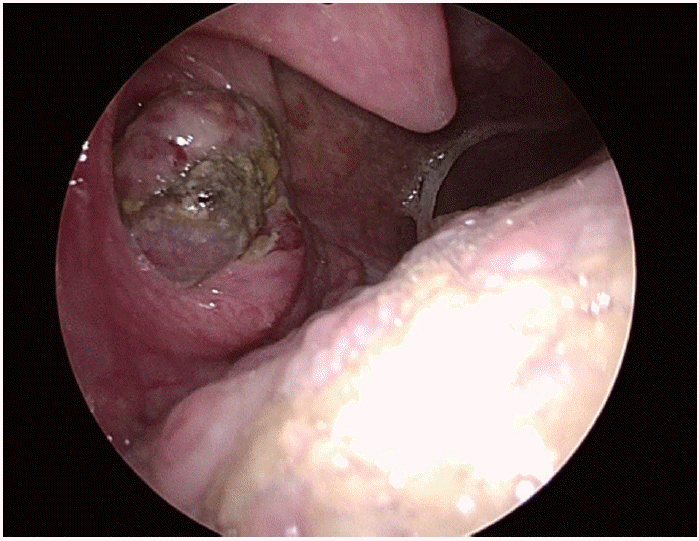

A 54-year-old man presented to a local clinic with a 2-week history of throat foreign-body sensation and blood-tinged saliva. On physical examination, an oval ulcerative lesion was observed on the right tonsil, and biopsy suggested pleomorphic sarcoma or a poorly differentiated malignant tumor, and he was referred to the otolaryngology department of our hospital (Fig. 1). There was no history of alcohol use, and he had a smoking history of half a pack per day for more than 30 years. He had no notable medical history other than hyperlipidemia.

Endoscopic view at the initial outpatient evaluation showing an ulcerative, protruding mass in the right palatine tonsil.

After the second course of radiotherapy during treatment, neck CT showed disappearance of the right tonsillar lesion, and radiotherapy was concluded while immunotherapy was continued. After three cycles of immunotherapy, neck CT showed no residual lesion in the right tonsil (Fig. 4A), and chest CT showed marked reduction in the size of the left primary lung cancer and the metastatic hilar lymph node (Fig. 4B). Abdominal CT also showed resolution of the small bowel lesion previously identified. On outpatient endoscopic re-evaluation, the ulcerative mass previously observed in the right tonsil had resolved and no active mass was identified (Fig. 5). The patient is currently being followed while maintaining immunotherapy.